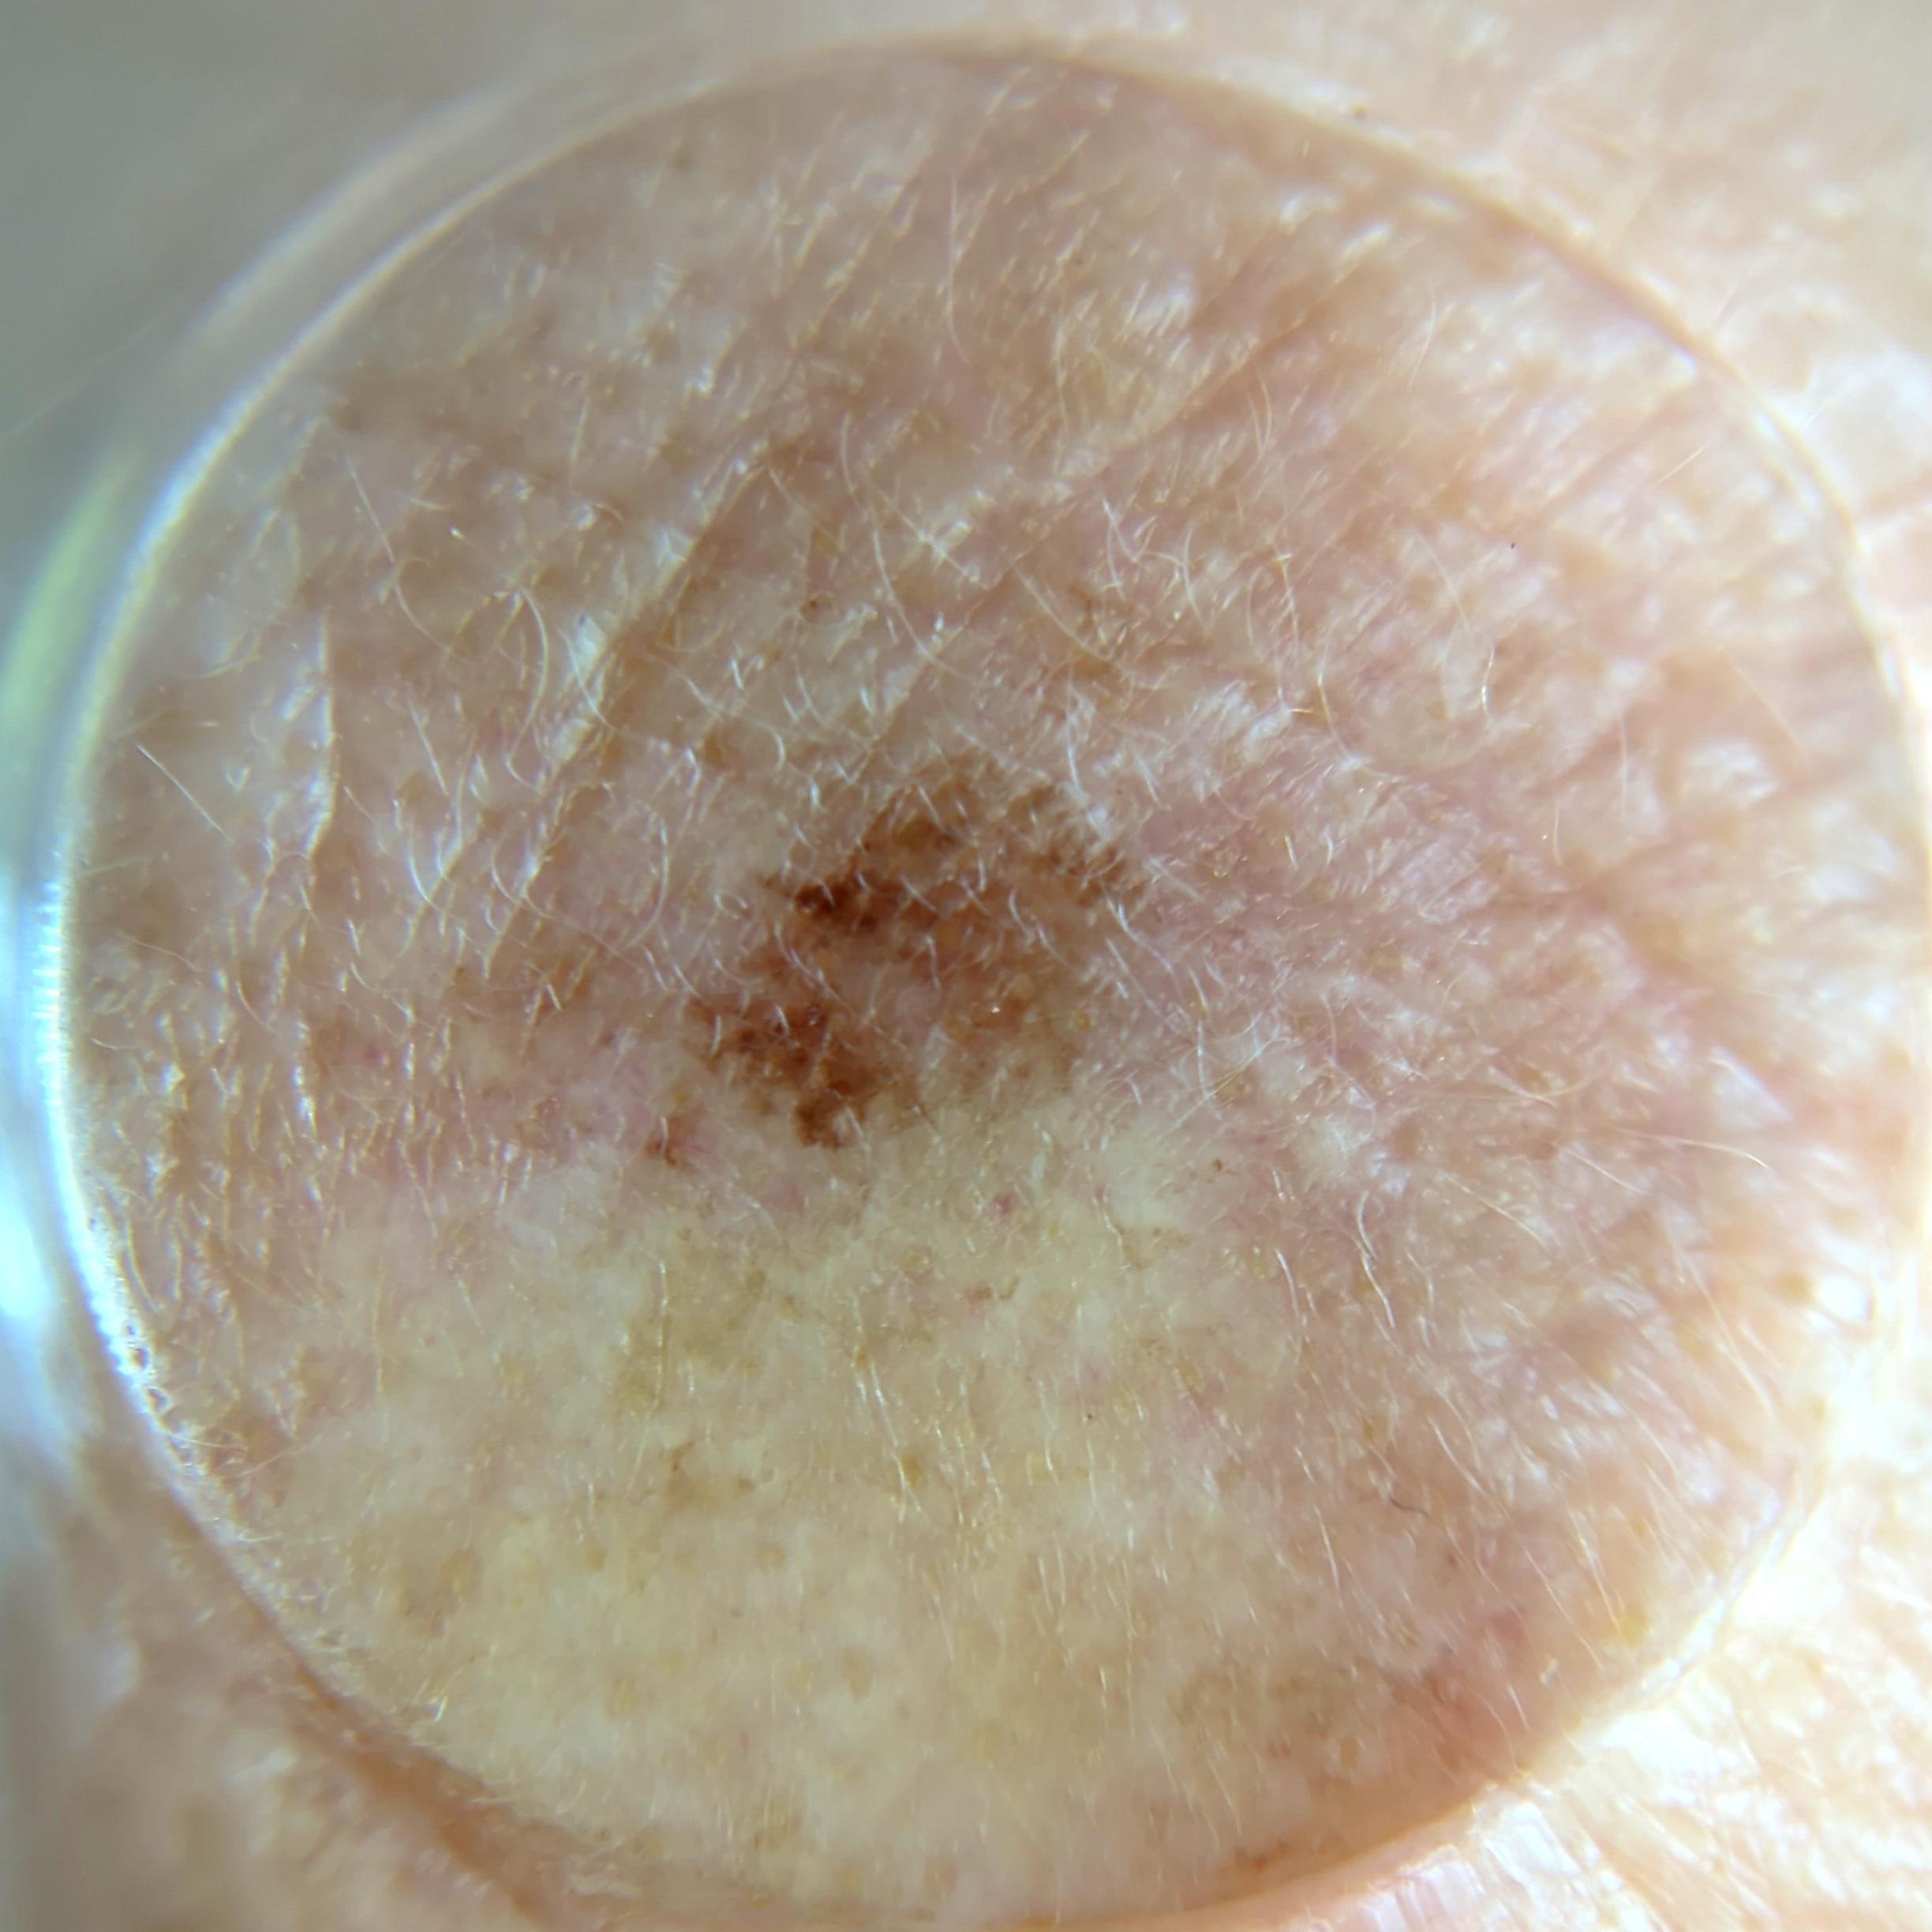

ISIC_7354512

image_type dermoscopic

lesion_id IL_4454105